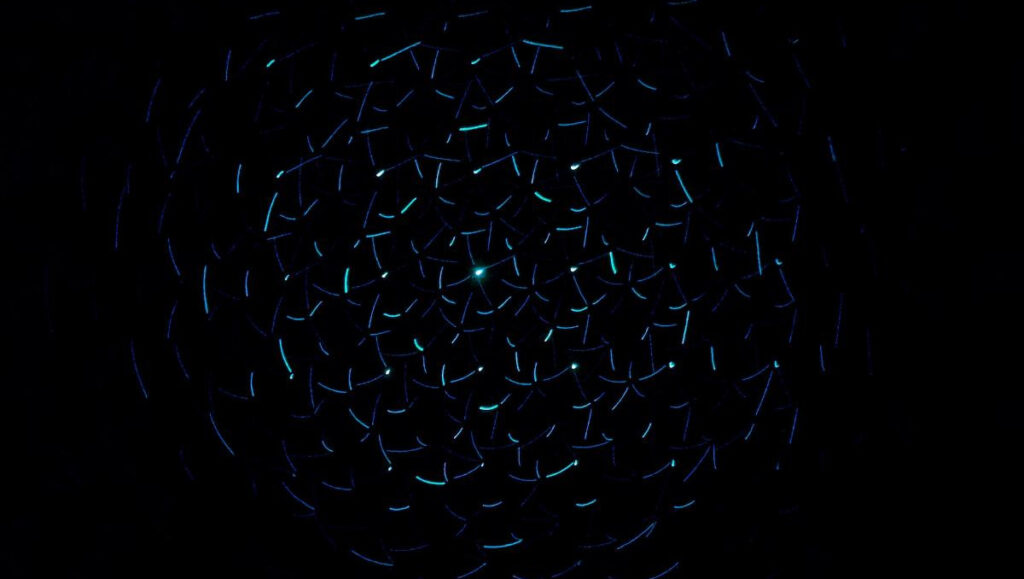

اعتمدت الدراسة على تحليل نشاط الدماغ لدى 142 شخصًا يعانون من آلام الظهر المزمنة و51 مشاركًا طبيعيًا. خلال التجربة، استمع المشاركون إلى أصوات مزعجة أثناء إجراء تصوير بالرنين المغناطيسي.

- نشاط مفرط في القشرة السمعية.

- زيادة النشاط في منطقة «الجزيرة» المسؤولة عن الإحساس والمشاعر.

- انخفاض في نشاط مناطق التنظيم العاطفي.